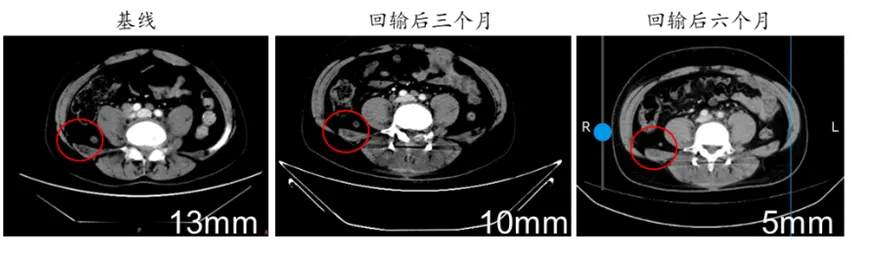

有效性方面,疾病控制和疗效呈现明显的剂量相关性。疗效在中高剂量中更为显著,其中75%患者出现持续肿瘤病灶缩小并代谢活性降低,少数患者甚至实现了肿瘤病灶100%持续完全缓解(CR)。

在疾病控制方面,BRG01回输后的患者可以持续无进展生存超过6个月,目前还在持续随访中,相比于现有最优的疗法PD1抗体,显示出显著延长的抗肿瘤效果以及患者的无进展生存期。